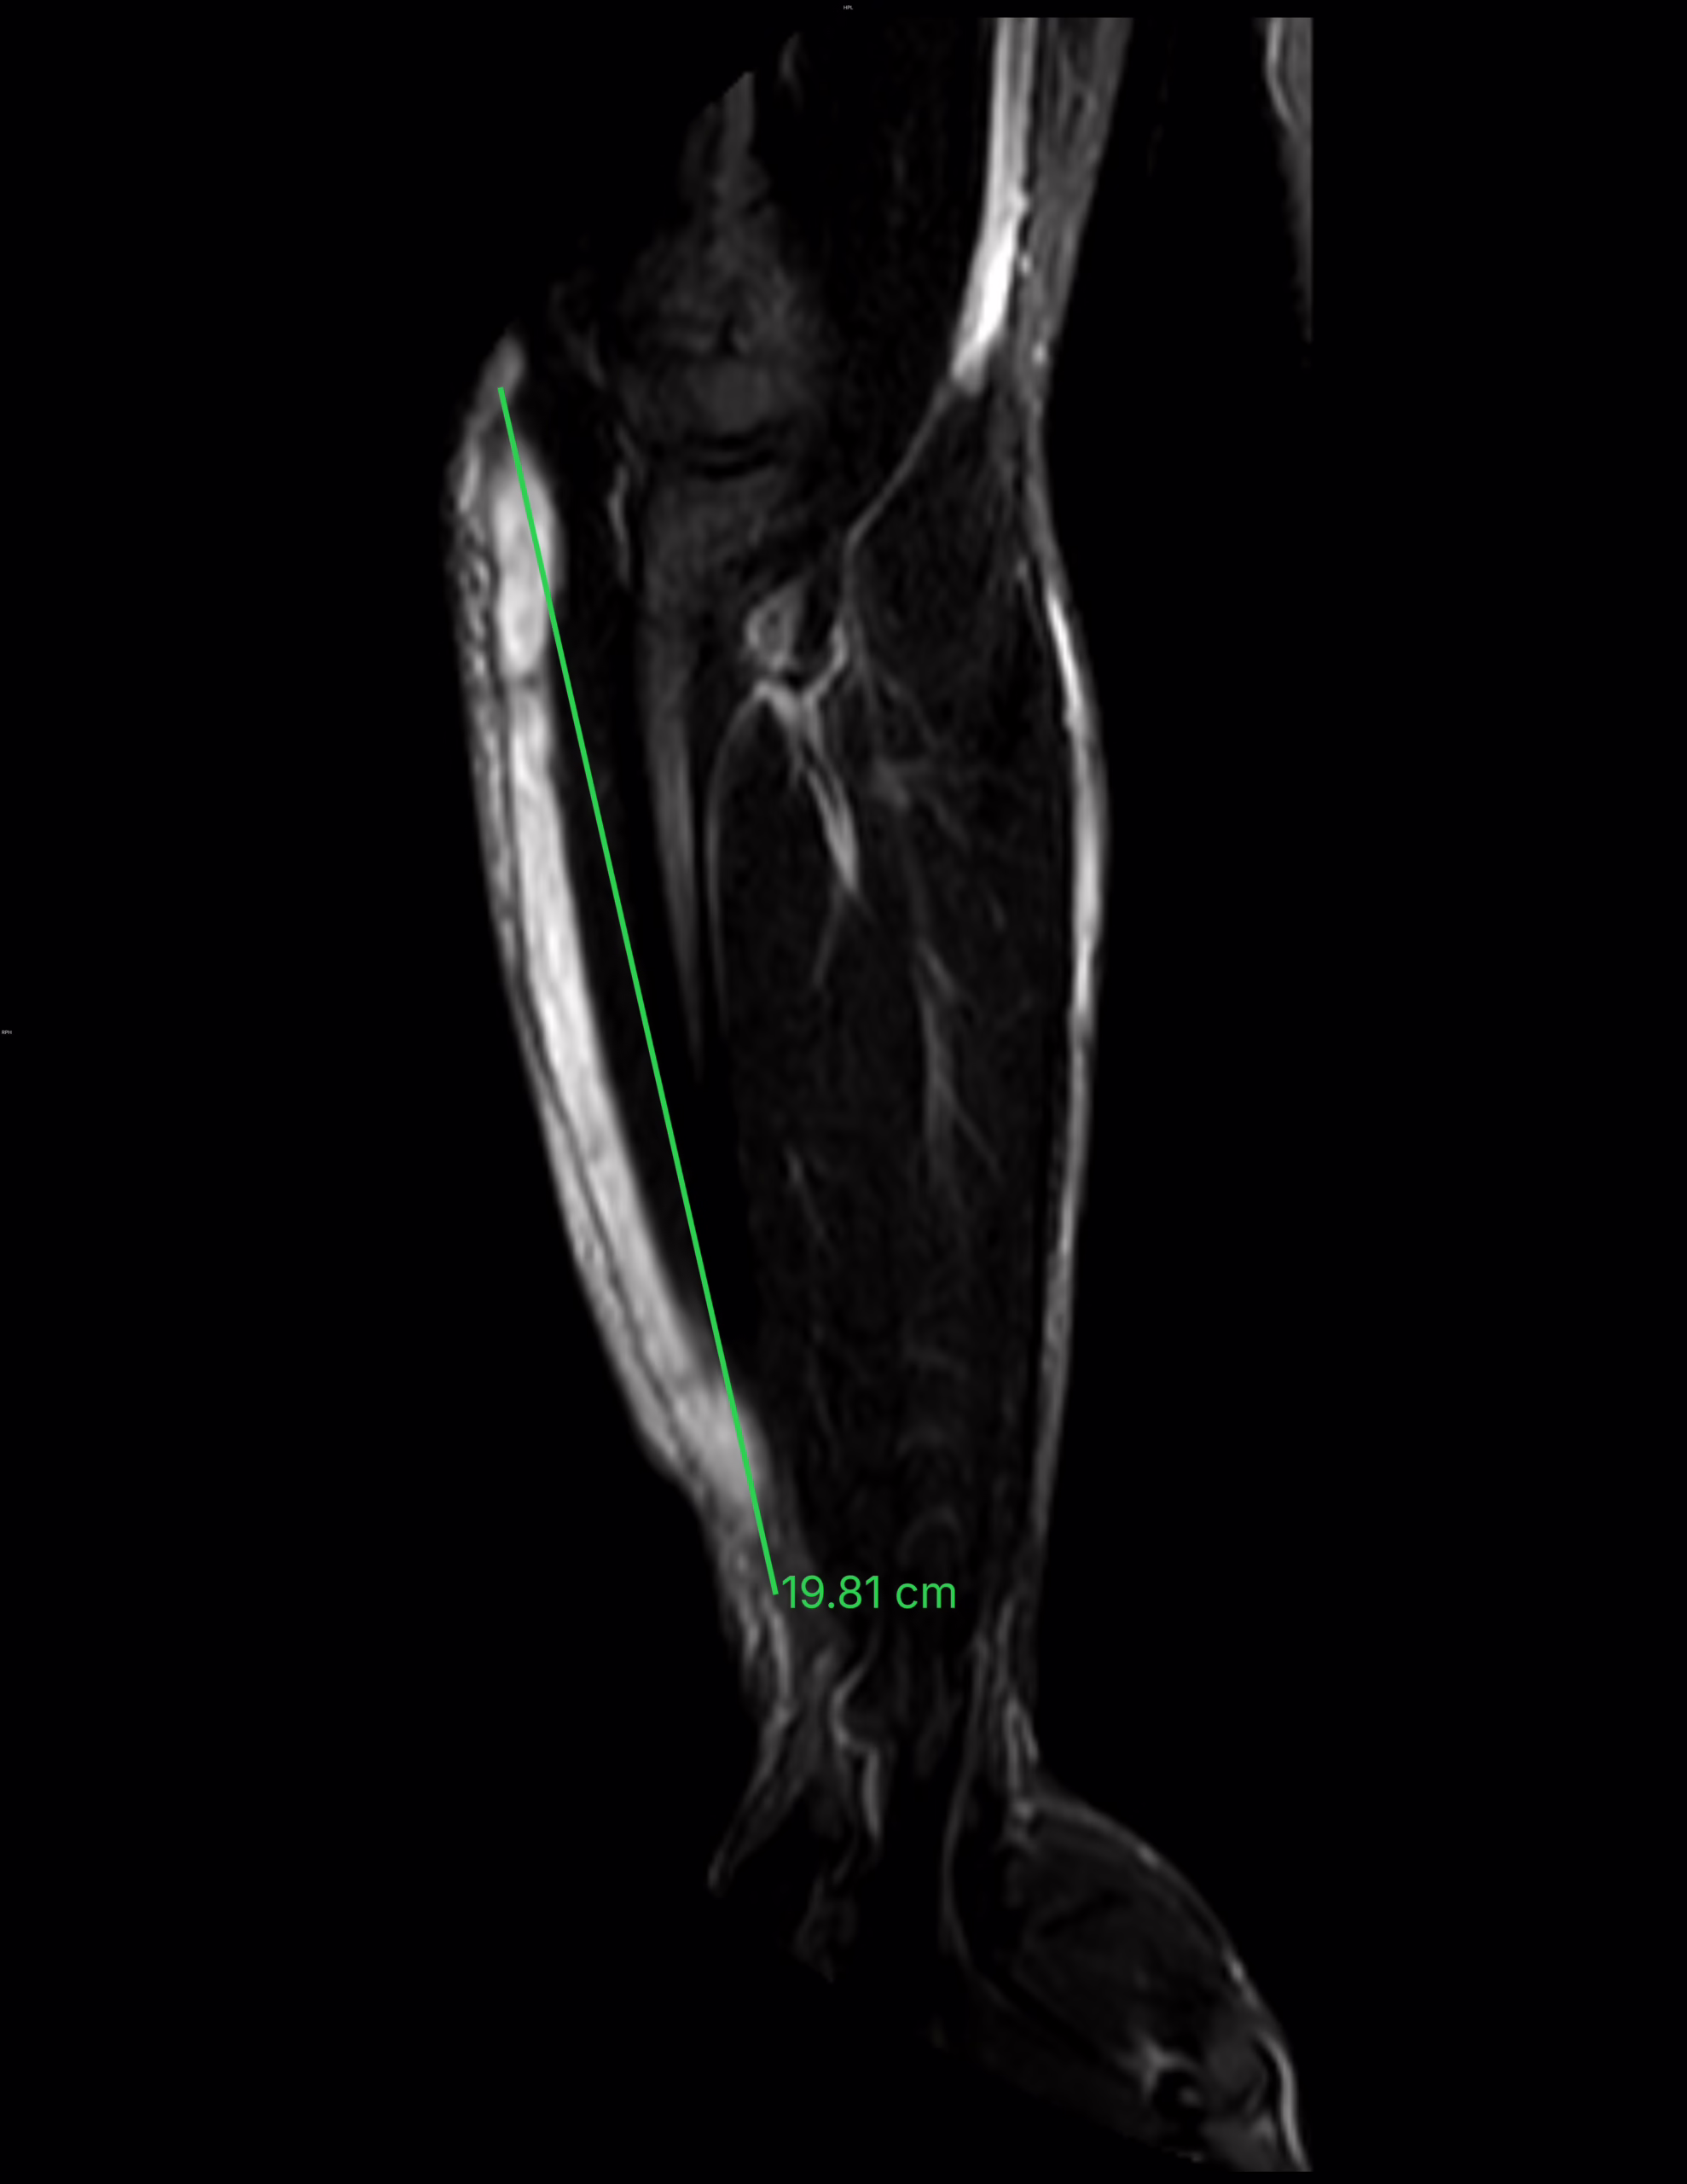

antebrazo existe una colección superficial a la musculatura que tiene intensidad de señal heterogénea por zonas octubre 27, 2025 drfroy Deja una respuesta Cancelar la respuestaTu dirección de correo electrónico no será publicada. Los campos obligatorios están marcados con *Comentario * Nombre * Correo electrónico * Web Δ Este sitio usa Akismet para reducir el spam. Aprende cómo se procesan los datos de tus comentarios. Buscar Search for: Search Acceso Acceder Feed de entradas Feed de comentarios WordPress.org Amigos Casos clínicos enarm Como bajar de peso Oscar Blancarte panchosoft Vitalis Sigueme.